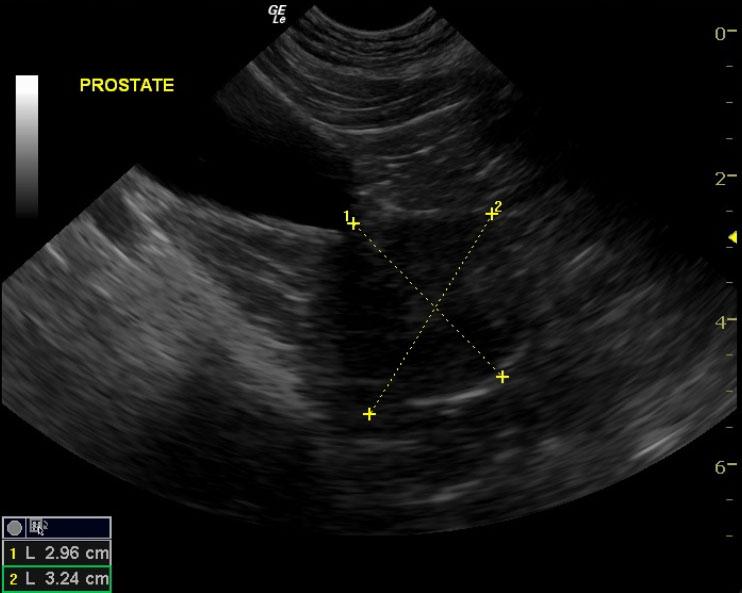

Enlarged prostate. Suspect carcinoma possible prostatitis

The prostate in this patient was 3.24 x 2.9 cm. It was very hypoechoic to the surrounding fat. Given the neutered male status it is strongly suggestive of prostatic neoplasia. However, this does appear uniform. Chronic prostatitis is a possibility, but less likely. Focal areas of mineralization were noted.